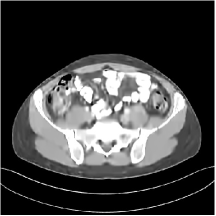

III.C.2. Simulation Framework, Reconstruction Results, and Comparisons

The synthesized low-dose clinical measurements are simulated from regular-dose images at a resolution of mm with a fan-beam CT geometry corresponding to a monoenergetic source at incident photon intensity . The sinograms are of size . The width of each detector column is mm, the source to detector distance is mm, and the source to rotation center distance is mm. We reconstruct images of size with the pixel size being mm mm.

We conducted experiments on one test slice used for parameter tuning (L067-slice 120) and four independent test slices (L109-slice 90, L192-slice90, L333-slice140, L506-slice 100) of the Mayo Clinic data. For PWLS-EP, we ran iterations using relaxed OS-LALM and set regularization parameter . We used the same as the phantom experiments for Algorithm 2. The process of selecting a general set of reconstruction parameters () for the Mayo Clinic test slices is identical to that for the XCAT phantom in Section III.B.2. The selected regularization parameter and the parameters that control the sparsity of the coefficient maps are for ST, , , , , for MARS2, , , , , , , for MARS3, , , , , , , , , , , for MARS5, and , , , , , , , , , , , , , , for MARS7, respectively.

Figs. 8, 9, 10, and 11 show the reconstructions of the four independent slices using the FBP, PWLS-EP, PWLS-ST, PWLS-MARS2, PWLS-MARS3, PWLS-MARS5, and PWLS-MARS7 schemes, respectively. Additional Mayo Clinic experimental results of the parameter tuning case (Fig. 15) are shown in the supplementary document. Table 1 lists the RMSE and SSIM values of reconstructions of the four independent test slices, with the best values bolded. Generally, the five and seven layer models provided the best RMSE and SSIM values. They outperform the single-layer model by HU in RMSE on average. However, the MARS5 and MARS7 models perform similarly. In order to strengthen the benefits of the multi-layer model, Table 2 lists the RMSE of the reconstructions in four different ROIs (shown in the reference of Fig. 11) with seven methods for slice 100 of patient L506. By observing the reconstructed images, we see that although the ST model achieves a cleaner reconstruction result than FBP and PWLS-EP, it still sacrifices some sharpness of the central region and suffers from loss of details. The deeper models have a somewhat more positive effect in terms of maintaining subtle features, which is clearly more essential to clinical diagnosis. Furthermore, as we will discuss later, after considerable parameter tuning, we found that the information contained in residual maps is gradually decreased with the number of layers, eventually vanishing at some layer, which suggests that very deep unsupervised models might not offer significantly better image quality.